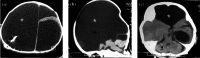

Kinesin super family (KIF) genes encode motor kinesins, a family of evolutionary conserved proteins, involved in intracellular trafficking of various cargoes. These proteins are critical for various physiological processes including neuron function and survival, ciliary function and ciliogenesis, and cell-cycle progression. Recent evidence suggests that alterations in motor kinesin genes can lead to a variety of human diseases, including monogenic disorders. Neuropathies, impaired higher brain functions, structural brain abnormalities and multiple congenital anomalies (i.e., renal, urogenital, and limb anomalies) can result from pathogenic variants in many KIF genes. We expand the phenotype associated with KIF4A variants from developmental delay and intellectual disability with or without epilepsy to a congenital anomaly phenotype with hydrocephalus and various brain anomalies at the more severe end of phenotypic manifestations. Additional anomalies of the kidneys and urinary tract, congenital lymphedema, eye, and dental anomalies seem to be variably associated and overlap with clinical signs observed in other kinesinopathies. Caution still applies to missense variants, but hopefully, future work will further establish genotype-phenotype correlations in a larger number of patients and functional studies may give further insights into the complex function of KIF4A.